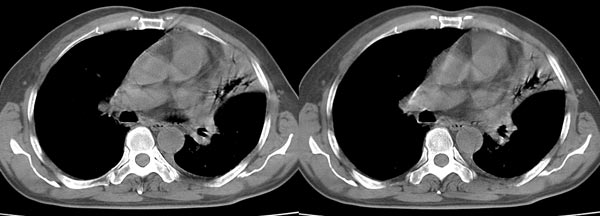

以下是引用dyqct在2006-4-1 22:20:00的发言:[br]左肺上叶明显萎陷、实变,支气管大部通畅,部分扩张,部分壁似见串珠状钙化。主动脉弓旁见肿大淋巴结。纵隔左移。左侧胸壁后缘见新月形高密度,边界清楚。[br] 考虑:1、左肺上叶肺不张伴支气管扩张(牵拉性),可能为支气管内膜结核所致。[br] 2、左侧少量胸腔积液。[br]

以下是引用piao001在2006-4-2 14:13:00的发言:[br]左肺上叶不全性不张,其内见钙化及扩张支气管,结合病史,考虑支气管内膜结核。建议支气管镜明确检查。